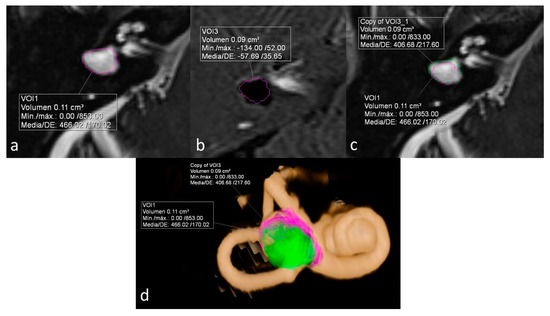

ELR ranged from 22% to 81%. It´s interesting to note that both extremes were present in the same patient, corresponding to a patient with right unilateral Ménière’s syndrome but with bilateral LSCCD (patient 4). On the dysplastic clinically affected side, ELR was 81% (Figure 2), whereas on the dysplastic clinically asymptomatic ear, ELR was barely 22% (Figure 3). In patients with unilateral LSCCD and available hydrops MR imaging (patients 3 and 5), the contralateral “normal anatomy” inner ear showed no signs of endolymphatic hydrops with endolymphatic ratios of less than 25% (not shown). The contralateral “normal anatomy” inner ear was asymptomatic.

Figure 3.

Same patient as in Figure 2. Left ear. No Ménièriform symptoms on this side. (a) Cisternography sequence showing LSCCD with volumetric measurement of total vestibular cavity volume. (b) 3D-IR-REAL sequence depicts volume of vestibular endolymph. (c) Overlay of both volumetric measurements in the cisternography image (d) 3D volume-rendered with color-coded volumes, obtaining an ELR of 22%, consistent with the lack of symptoms on this ear.